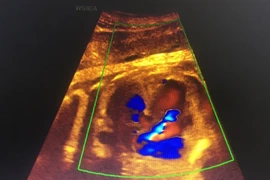

(khoahocdoisong.vn) - Các dải xơ buồng ối quấn thắt vào thai nhi không chỉ gây khoèo chân, cụt chi, tổn thương não, nội tạng và dị tật cho các bộ phận khác mà còn gây sẩy thai, thai lưu. Để cắt dải cơ buồng ối, Bệnh viện Phụ sản Hà Nội là đơn vị công lập đầu tiên trong cả nước thực hiện thành công phẫu thuật nội soi bằng laser quang đông bào thai trong bụng mẹ.

(khoahocdoisong.vn) - Khi mắc hội chứng truyền máu song thai nếu không được điều trị thì 90 - 100% thai sẽ chết. Còn nếu một trong hai thai chết thì 25% thai còn lại bị di chứng thần kinh nặng nề. Bệnh viện Phụ sản Hà Nội là bệnh viện đầu tiên trong cả nước thực hiện được kỹ thuật.

(khoahocdoisong.vn) - Siêu âm còn là phương pháp bắt buộc trong theo dõi sản khoa, giúp bà mẹ thêm an tâm về sự phát triển toàn diện của con trước khi chào đời.

(khoahocdoisong.vn) - Nhờ kỹ thuật hiện đại, bệnh viện Phụ sản Hà Nội đã phát hiện và theo dõi được một trường hợp có huyết khối xoang tĩnh mạch màng cứng ở thai nhi 29 tuần tuổi.